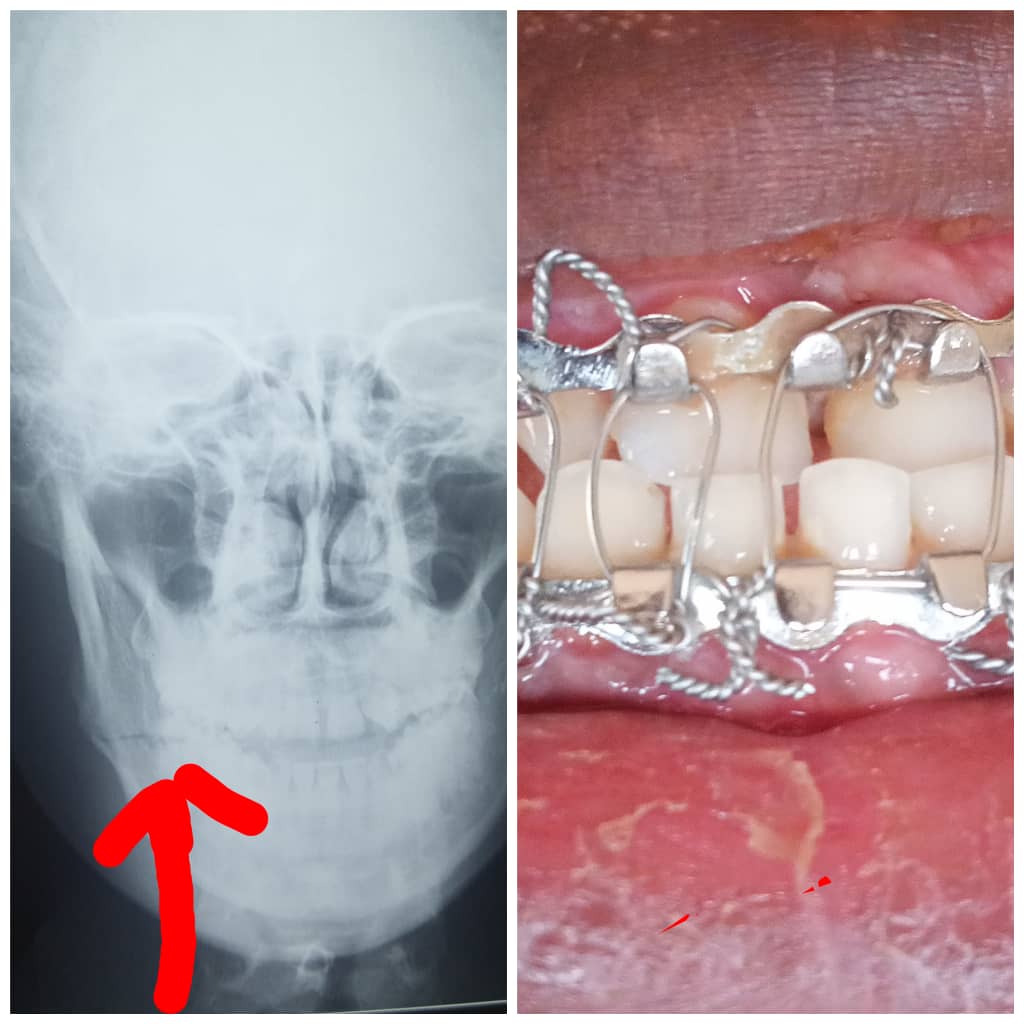

Experience specialized care for complex oral and facial conditions with our maxillofacial surgery expertise. From corrective jaw surgery to facial trauma repair, our skilled surgeons provide comprehensive treatments tailored to your needs.